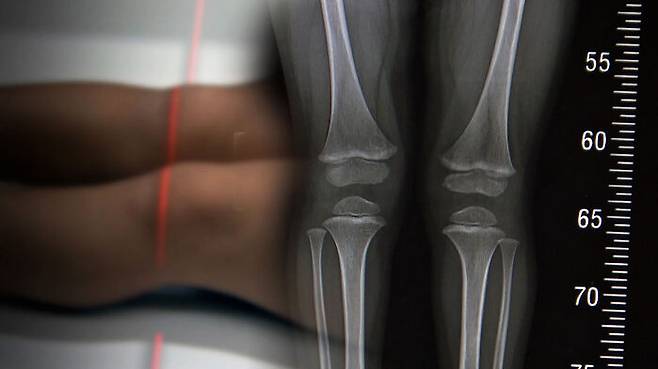

아빠 키와 엄마 키를 더해서 하는 거는 정말 추정치인 거고, 만약에 그게 맞다면 사실은 형제자매가 다 키가 똑같아야 되는데 그렇지 않잖아요. 이거는 사실은 경향을 보는 것뿐이고, 성장판을 찍는 거는 요새 높게 보고하는 데는 95%까지 보고합니다. 꽤 정확해요.

몸이 좀 커지고 말단 비대증이라고 해서 손이랑 턱이 커지죠. 암도 발생할 수 있고. 성인은 더 심각한 부작용이 생기기 때문에 절대 하면 안 되는데, 그런 작동을 하기 때문에 키도 크는 거죠. 어렸을 때는 성장판이 열려 있으니까.

성장이 끝나기 전에 맞아야 돼요. 사춘기가 시작되기 전. 사춘기 땐 엄청나게 성장호르몬이 나오기 때문에 그때 맞는 건 의미가 없거든요. 사춘기 전에 맞아야 됩니다.